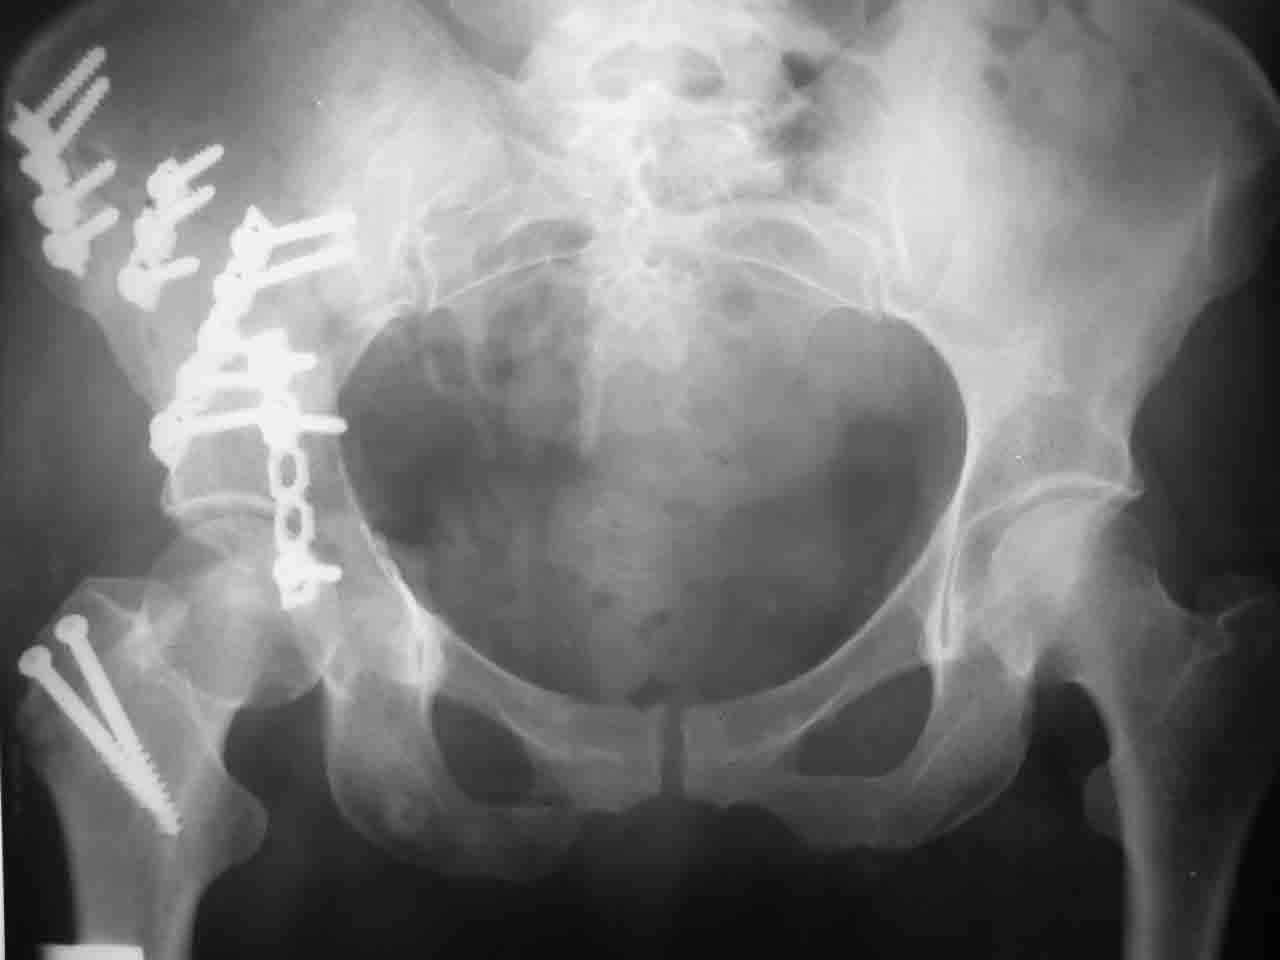

форуме и скелетном вытяжении. С репозицией и фиксацией задней колонны и отдельно задне-верхней стенки впадины проблем не возникло. Послеоп. Рг граммы в приложении. Если возникнут какие-либо дополнения или поправки - был бы признателен.

Спасибо за комментарии и рекомендации. Откровенно говоря, больного я прооперировал на прошлой неделе, через 5 дней после аварии и проблем с ним пока никаких нет, на удивление при достаточно обширной диссекции (илиофеморальный доступ) болей практически нет, так что больной самостоятельно садится в кровати, выполняет активные движения в оперированном суставе, сгибая до 60 градусов пока, далее с ассистенцией.

Причиной обращения к сообществу были возникшие непосредственно после операции сомнения и разочарования полученным качеством репозиции: а надо ли было трогать перелом вообще, репозиция передней колонны технически была очень сложна для меня, хотя реконструкции была в той же последовательности, что Д-р А.В.Рунков рекомендовал, в какой-то момент безуспешных манипуляций стал думать о *вторичной конгруэнтности*, которую не так давно обсуждали на